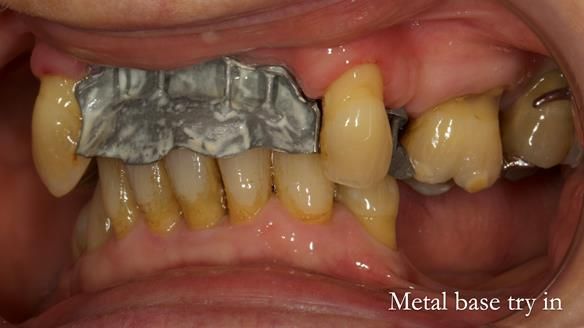

In this edition, I present the removable partial denture treatment for Jean, an 80-year-old woman with a sore mouth caused by a soft tissue-supported 'gum stripper' acrylic denture and a clenching habit. Below, I outline the step-by-step process of her treatment. It wasn't straightforward; I had to remake the denture after it fractured to achieve a satisfactory result. Each patient is unique, and sometimes a new RPD serves as a prototype. Occasionally, I need to make adjustments, learn from any mistakes, and refine the design to get it right.

The treatment has been a success over the past 4 years.